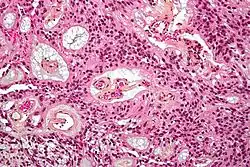

Micrograph of an ependymoma. H&E stain.

Ependymomas are composed of cells with regular, round to oval nuclei. There is a variably dense fibrillary background. Tumor cells may form gland-like round or elongated structures that resemble the embryologic ependymal canal, with long, delicate processes extending into the lumen; more frequently present are perivascular pseudorosettes in which tumor cells are arranged around vessels with an intervening zone consisting of thin ependymal processes directed toward the wall of the vessel.[5]